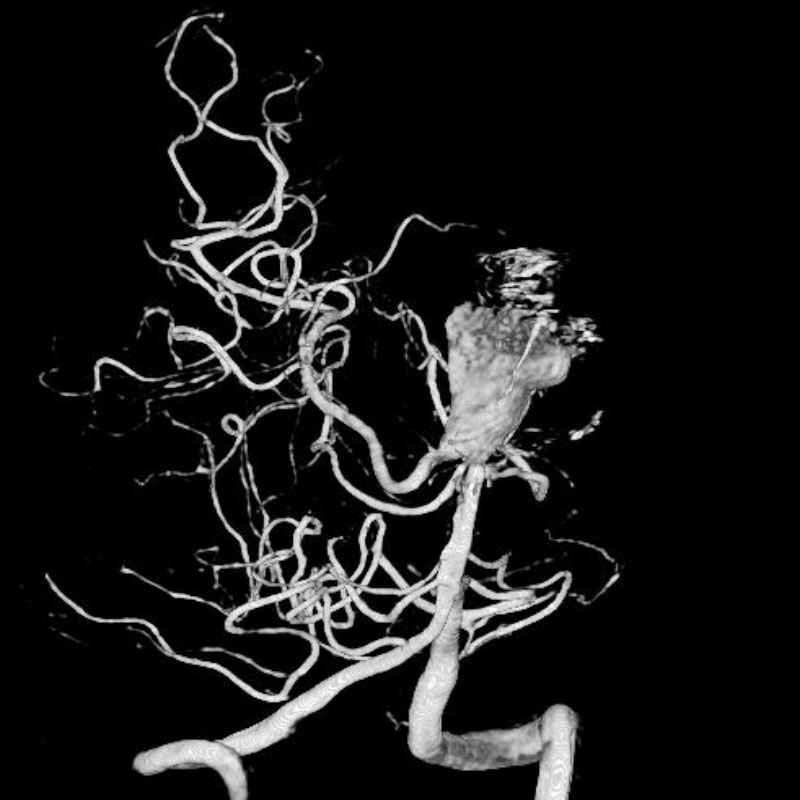

脳動静脈奇形

血管塞栓術

松田/濵田/元永